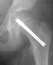

The patient was admitted to the hospital, placed on strict bedrest,

and he had an in situ pinning of his right hip the next day. There were

no postoperative complications, and he was discharged one day later. By

the time of his follow-up visit three weeks later, he was riding his bike

and had discarded his crutches. An AP pelvis

and frog-leg lateral radiographs of both hips were obtained which were

normal. At his three-month follow-up visit, the patient complained of a